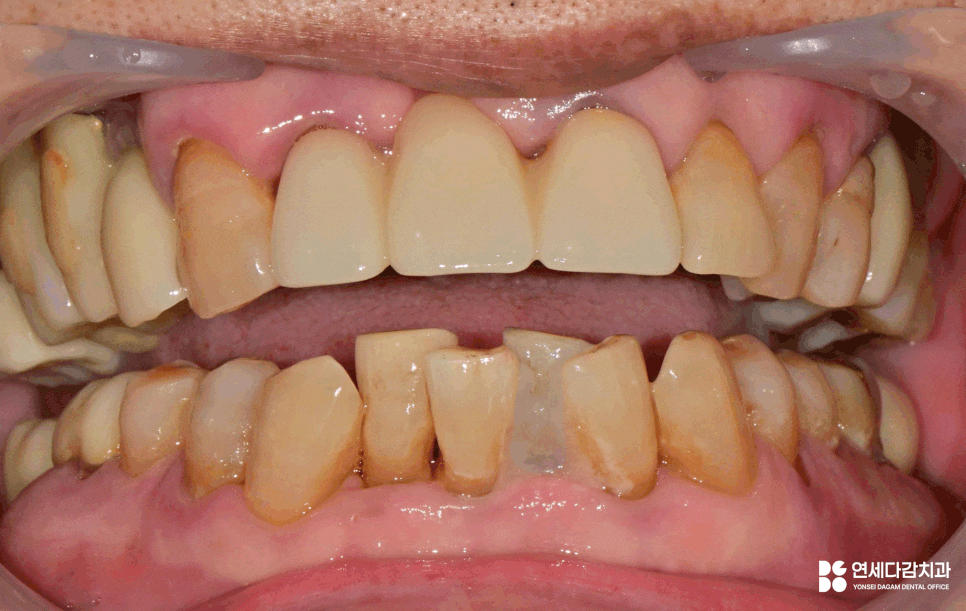

그럼, 어떤 상황으로 이어지는지

예시 자료로 살펴보도록 하겠습니다.

그러나 치주 질환의 주된 원인이 되는

치석이 잇몸 하방으로 내려가게 되면

치주염으로 발전하게 됩니다.

이때는 치석이 독소 같은 작용을 하면서

치조골을 녹이는 문제를 일으킬 수 있습니다.

결국 치근을 제대로 잡아주지 못해

치아는 버틸 힘을 잃고 흔들리기 시작합니다.

심한 경우 외상이나 사고가 없더라도

자연스럽게 탈락하는 문제로 이어집니다.

이러한 변화를 방지하기 위한 방법 중 하나가

바로 '잠간 고정술'입니다.

이는 탈락한 부위 주변 환경을 고려해

간단한 레진 등의 재료를 이용하여

임시로 메워주는 방법으로 진행됩니다.

다만, 개롱역 치과 에서 보여드리는 것과 같은

발치된 치아를 이용한 방식 같은 경우

일반적인 방법과는 다릅니다.

보통 흔들리는 곳과 그렇지 않은 치아를

서로 접착하면 유지력을 잃게 될 수 있습니다.

이 경우 환자분께서 발거치아를

꼭 다시 붙이시길 원하셨습니다.

환자분이 충분한 설명을 이해하고

사용에 제한을 두는 조건으로 처치를 원할 경우

예외적으로 시행되기도 합니다.